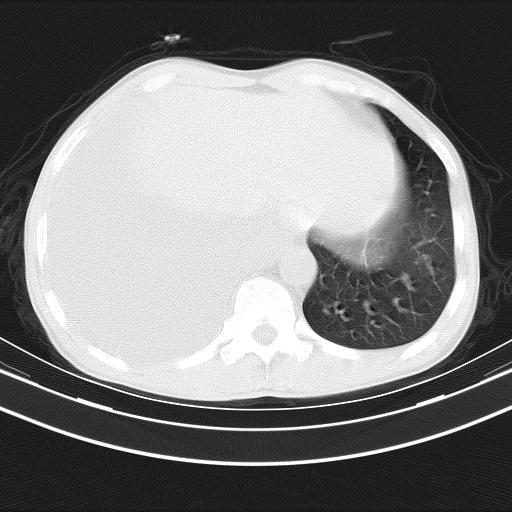

男性,44岁,结核病史多年。现胸闷气短,咳嗽,偶咳血。

右侧胸腔积液

右肺下叶不张

双肺多发结节影最分空洞形成考虑占位不除外结核

1、右侧大量胸腔积液伴右肺压缩性膨胀不全,建议抽液治疗后复查 2、两肺继发性tb伴空洞形成。

1)两肺继发性肺结核伴空洞形成,左肺多发性结核球。2)右侧大量胸腔积液伴右肺部分膨胀不全。3)纵隔淋巴结肿大。